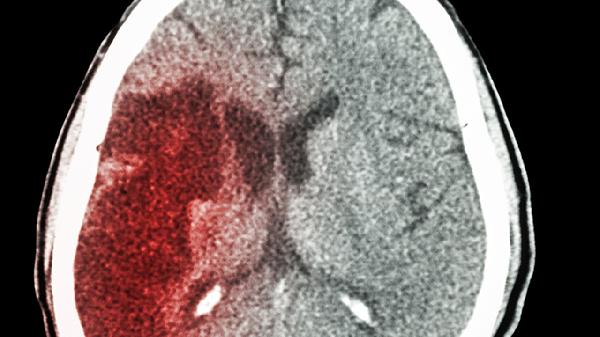

5、外伤性脑血肿

轻度颅脑外伤后遗留的脑血肿吸收期可使用脑得生丸辅助治疗。其化瘀功效能加速血肿消散,改善头痛、眩晕等症状。需定期复查头颅CT,严重者需联合七叶皂苷钠片脱水治疗。